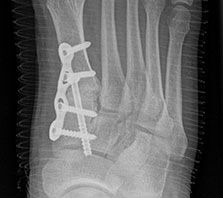

Standard ist die belastete Röntgenaufnahme des Fußes dorso-plantar und seitlich. Günstig ist eine Röhrenkippung von 10°-20°, um die Gelenke der Lisfranc-Linie einsehen zu können.

Ergänzend kann eine Schrägaufnahme hilfreich sein. Bei Metatarsalgien oder Pathologien der Sesambeine liefert die Sprinteraufnahme zusätzliche Informationen. Bei einer Pes planovalgus Fehlstellung wird ergänzend ein Saltzman view durchgeführt.

Bezüglich der Operationstechniken wird von früher häufig durchgeführten alleinigen Weich­teileingriffen am Großzehengrundgelenk aufgrund hoher Rezidivraten abgeraten 15. Die Operation nach Mc Bride mit lateralem Release, Exzision des lateralen Sesambeins, Abtragen der Pseudoexostose, Sehnenetransfer des M. adductor hallucis und mediale Kapselraffung zeigte unbefriedigende Mittel- und Langzeitergebnisse 16. Die Cerclage fibreux (mediale Kapselraffung) und das laterale Kapselrelease wird heute in Kombination mit einem knöchernen Eingriff angewendet. Bezüglich des Einsatzes von minimalinvasiven Operations­techniken vor Wachstumsabschluss liegen bisher keine Daten vor. Alle Osteotomien lassen sich nach Bedarf miteinander kombinieren. Es ist darauf zu achten, dass Osteotomien keine offenen Wachstumsfugen verletzen.